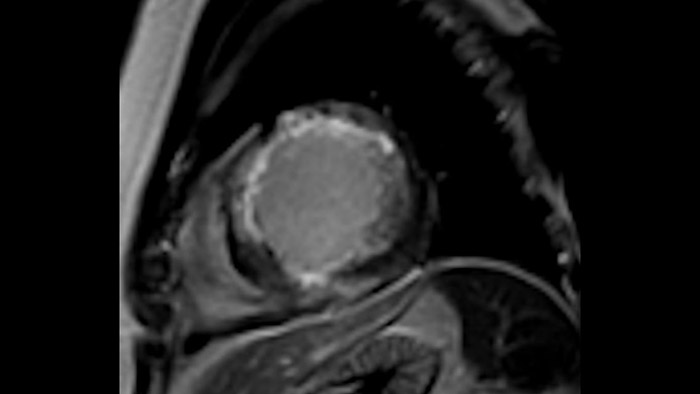

L'utilità diagnostica e prognostica della RM cardiaca è in continua crescita. È possibile valutare l'anatomia e la funzionalità cardiache utilizzando acquisizioni cine, ottenere informazioni sulla perfusione e vitalità del tessuto cardiaco, visualizzare potenziali edema con la sequenza Black Blood, accedere e persino quantificare la caratterizzazione dei tessuti con CardiacQuant.